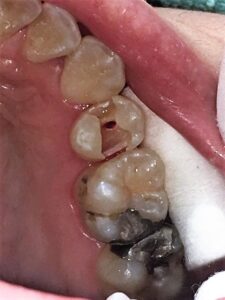

下の写真の患者さんは虫歯の治療中に露髄(歯の神経が見えてしまうこと)してしまいました。術前に神経を保護するMTAセメントを使用したいと申し出があったため直接覆髄法を行いました。

虫歯除去後。歯の中心部に神経が見えてしまいましたが、神経はまだしっかりと生きていました。

MTAセメントにて覆髄しました。